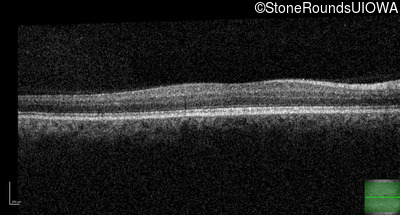

Congenital Stationary Synaptic Dysfunction (IA2g)

Congenital Stationary Synaptic Dysfunction (IA2g)

| Congenital Stationary Synaptic Dysfunction | CABP4 | Arg49Stop CGA>TGA | IVS1+1 G>T | AR |